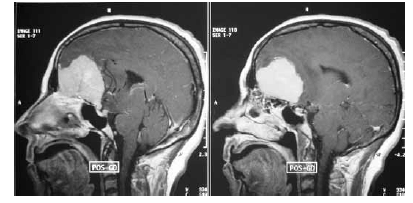

Considerando a figura acima, que mostra o resultado do exame de imagem de um paciente, julgue os itens seguintes.

As imagens mostram lesão com características radiológicas de malignidade, sendo indicada ressecção cirúrgica completa e tratamento oncológico do paciente com temozolamida.

Fatores hormonais estão envolvidos no desenvolvimento da doença do referido paciente devido à presença de receptores de hormônios sexuais nas células neoplásicas.

A lesão identificada no exame de imagem em questão é frequente em pacientes com neurofibromatose tipo 2.